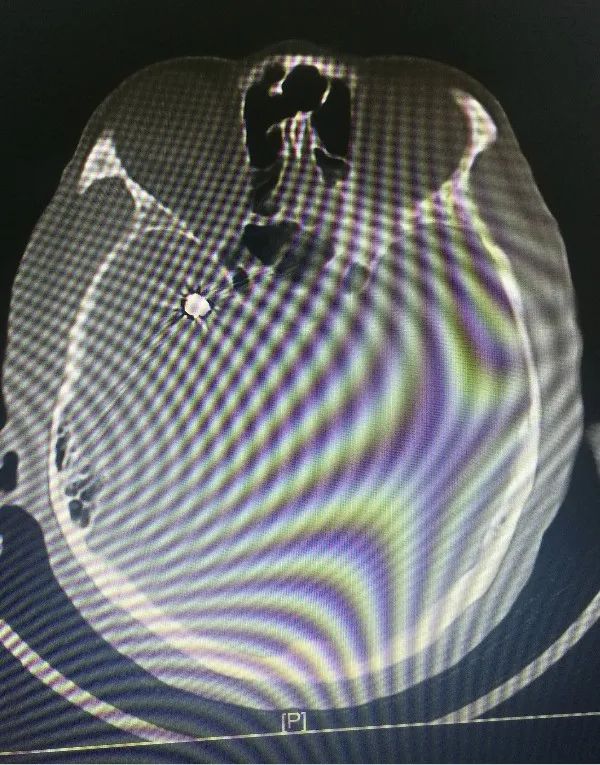

近日,省人民医院神经外科为一位高龄动脉瘤患者施行了介入治疗,成功栓塞了破裂的大脑中动脉瘤。患者因突发晕厥后头痛不适入院,急诊行颅脑CT检查提示蛛网膜下腔出血,行颅脑CTA检查后证实患者存在右侧大脑中动脉瘤。患者高龄,既往基础病多,高血压病、糖尿病、冠心病、双侧颈动脉硬化、双侧腹股沟疝术后等,手术风险较大,经家属签字同意后,当日急诊全麻下行“右侧大脑中动脉瘤介入栓塞术”,术中见血管迂曲明显,导管到位艰难,经过努力,手术顺利结束。术后予多次腰椎穿刺术释放血性脑脊液,患者头痛头晕症状渐缓解。患者住院治疗10天后顺利康复出院,未留后遗症。